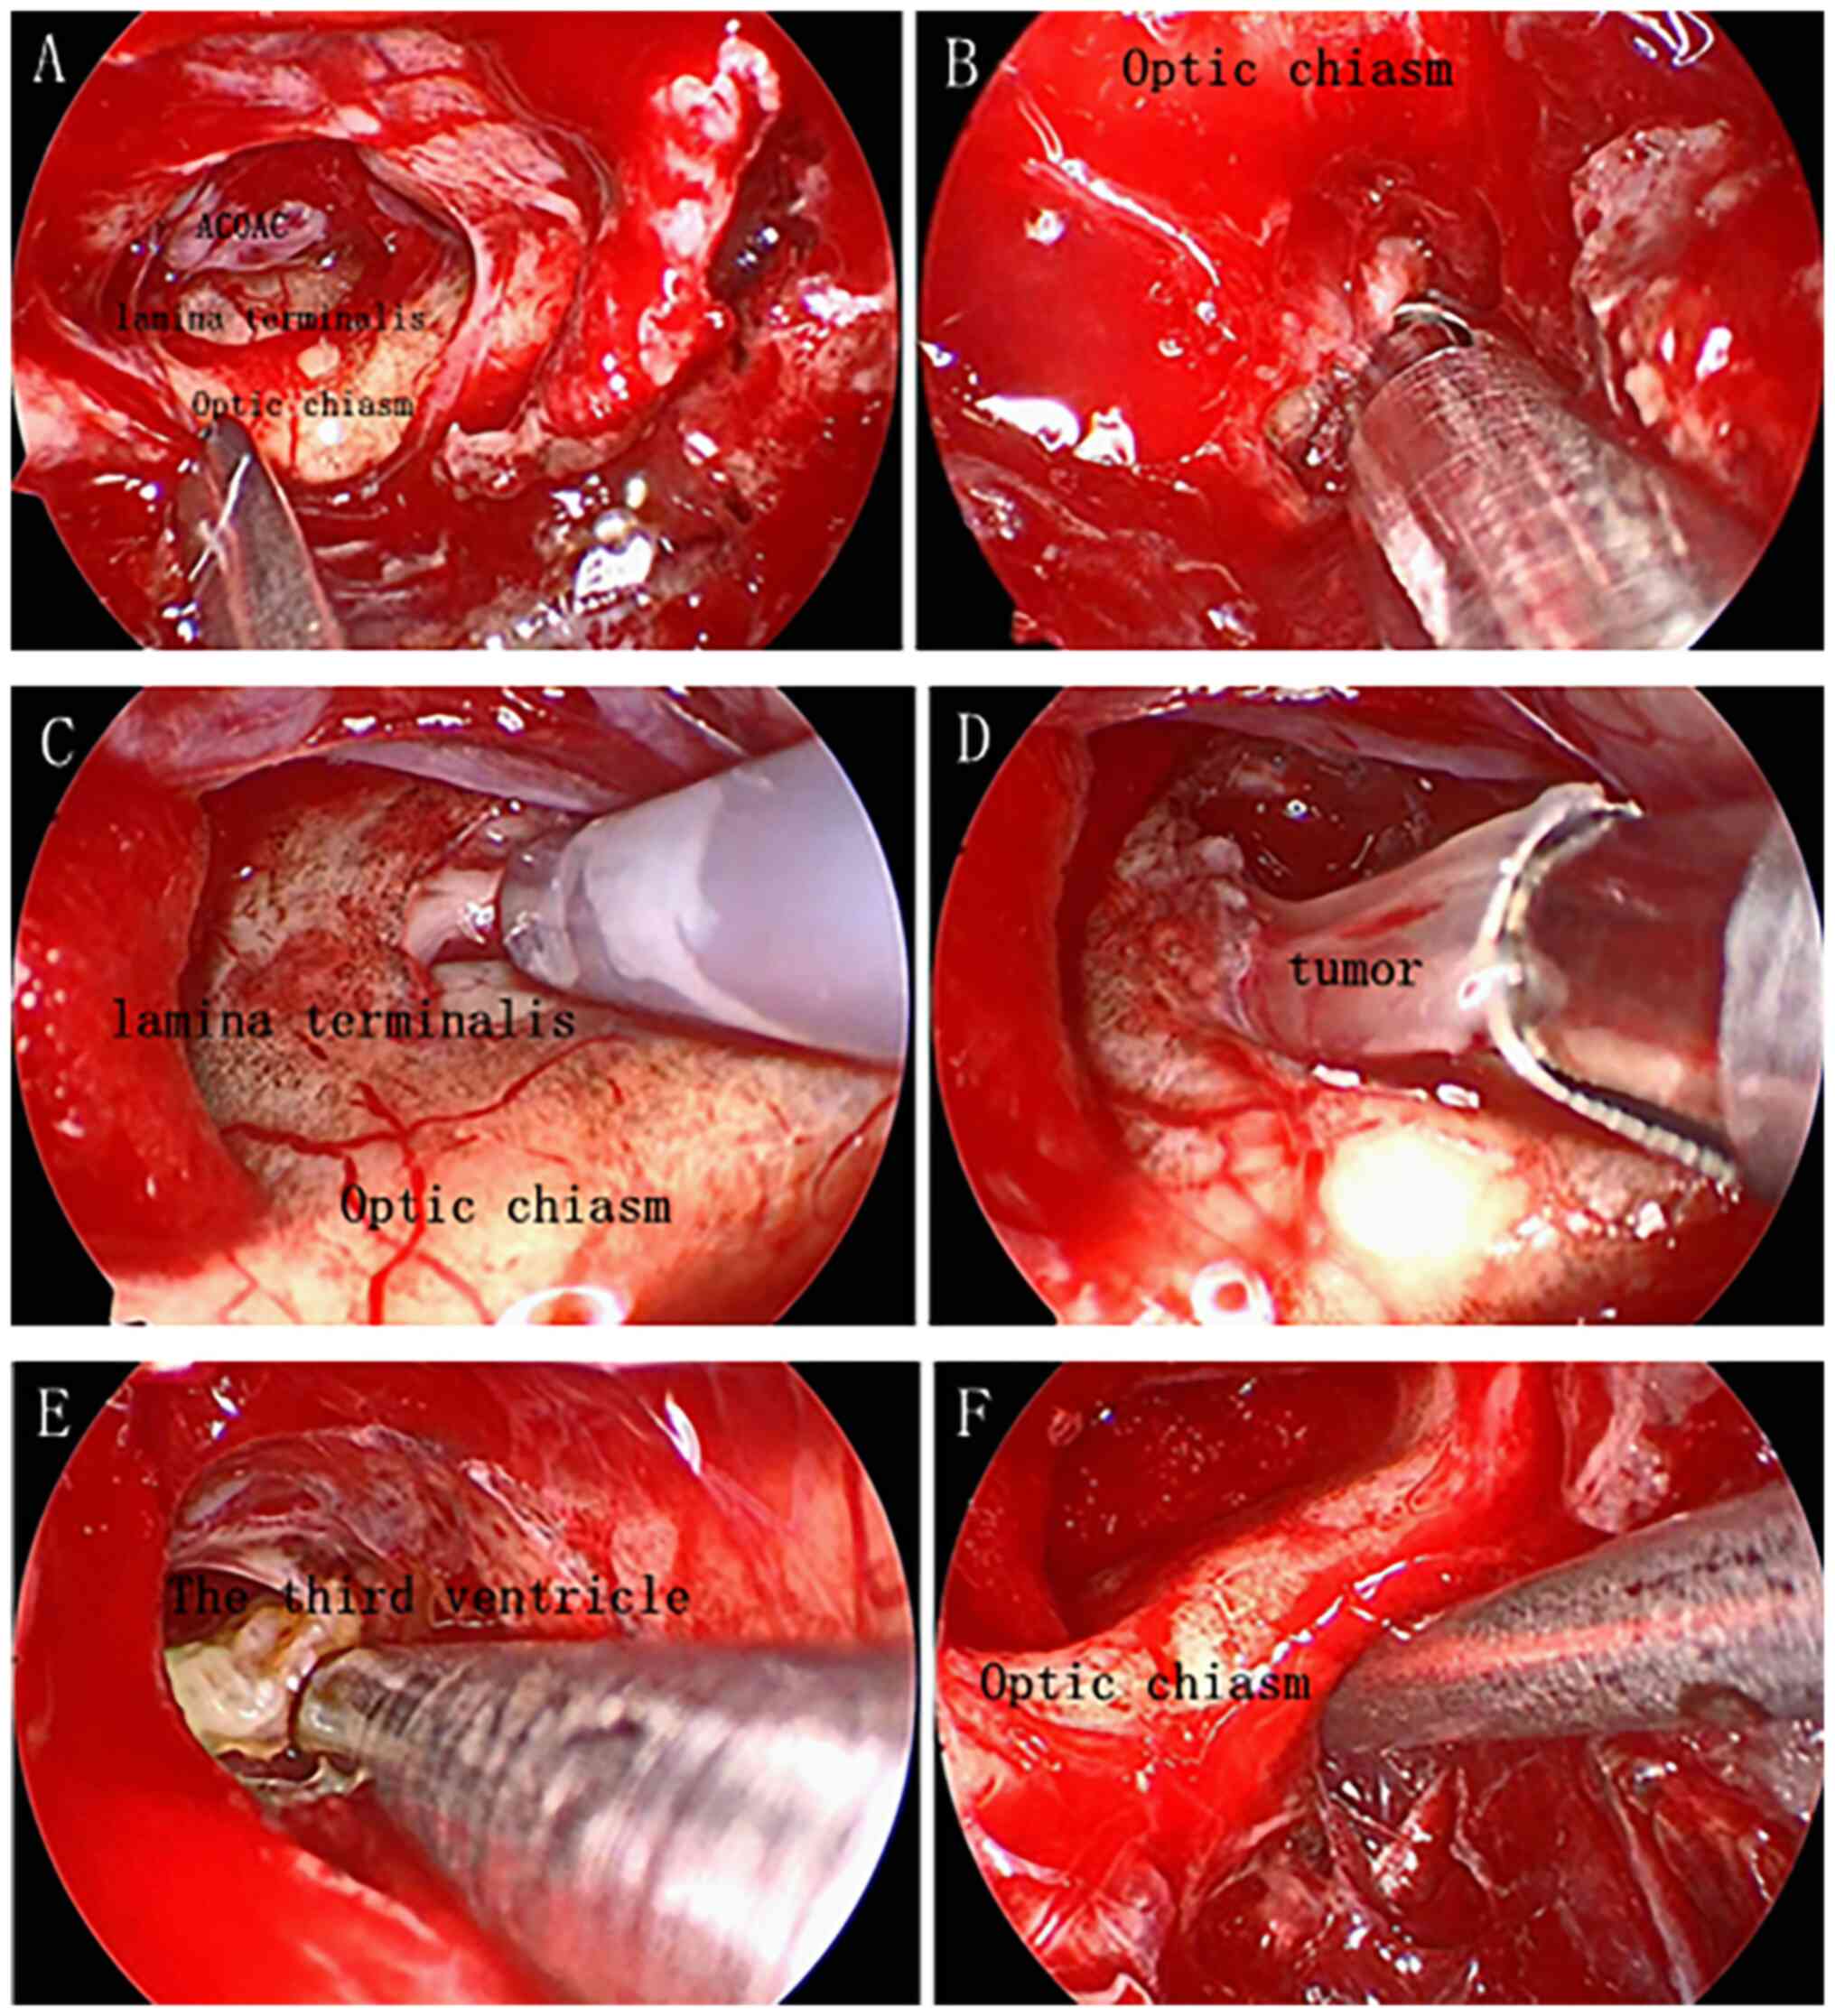

Craniopharyngioma resection and aneurysm clipping performed simultaneously by pure endoscopic endonasal approach: A case report and literature review

Craniopharyngioma is one of the most challenging issues for neurosurgeons as a brain tumor. Among the approaches of neurosurgery, in comparison to craniotomy, the endoscopic endonasal approach (EEA) has risen in popularity over the last two decades; unruptured intracranial aneurysms are relatively commonly found in the general population. The EEA as a new paradigm in the treatment of aneurysm has been reported to successfully clip dozens of cases of intracranial aneurysm. However, when reviewing the domestic and foreign literature, it appeared that cases of craniopharyngioma complicated with intracranial aneurysm purely treated by EEA have not been reported so far. In the present study, the published literature regarding endoscopic endonasal surgery for craniopharyngioma and intracranial aneurysms was reviewed, accompanied with a case of craniopharyngioma complicated with intracranial aneurysm, both of which were simultaneously treated by EEA.